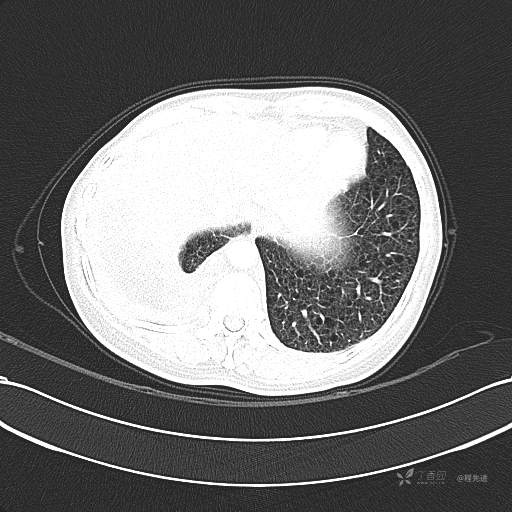

患者性别:女

患者年龄:51岁

简要病史:胸闷半年